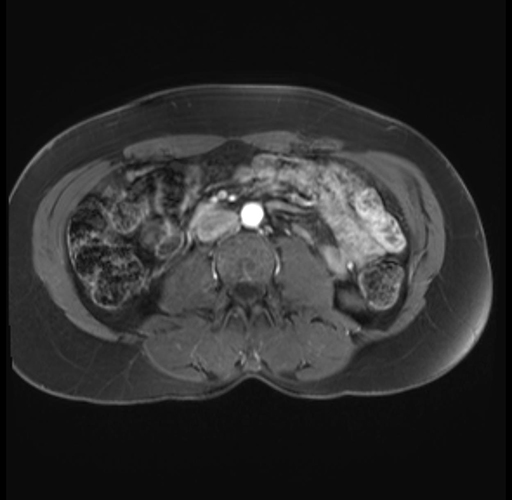

Imaging Analysis

Look through the patient's CT scan to identify any areas of concern for the necessary procedure.

Based on your CT findings, which issue(s) are present and would give reason for "planned slowing down moment(s)" in this case?

Considering a standard distal pancreatectomy procedure, what step(s) of the operation would you do differently in this case?